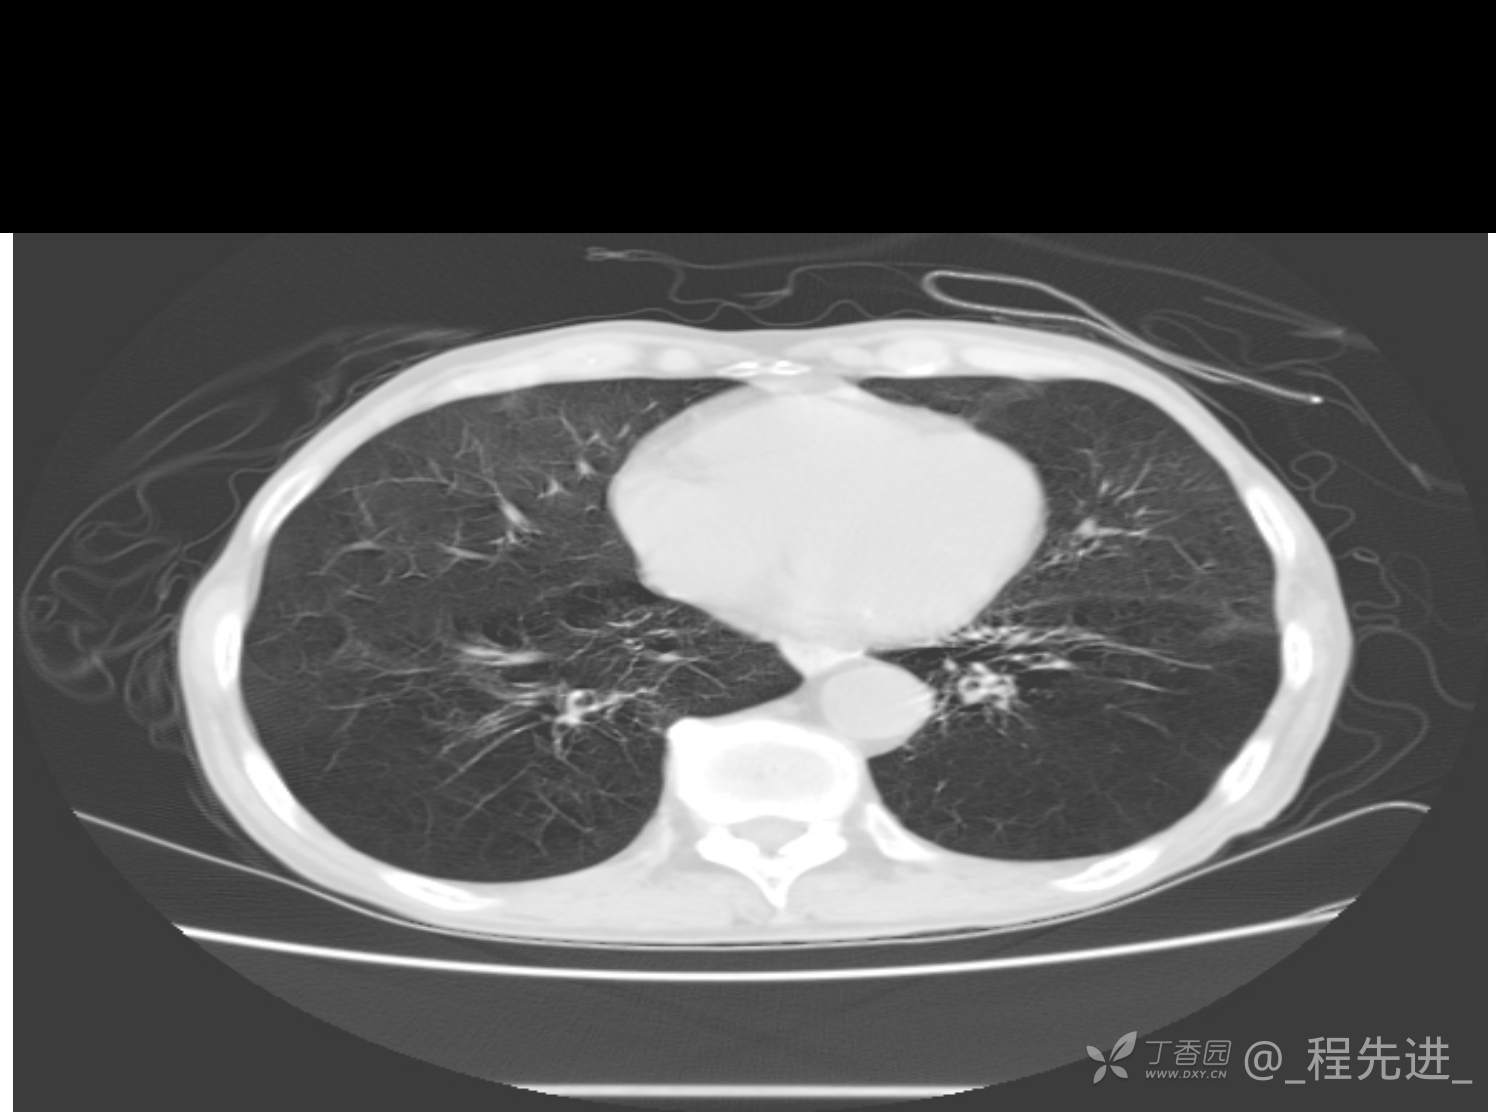

患者性别:男

患者年龄:81岁

简要病史:反复咳嗽、咳痰20余年,加重1周。两肺呼吸音低,可闻及散在干湿啰音。